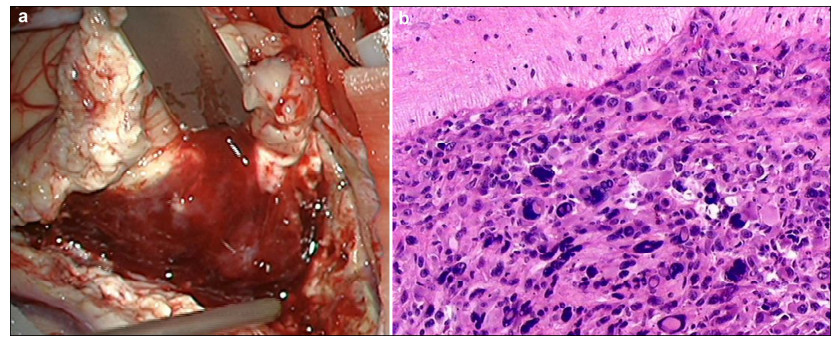

2 Case reportA 34-year-old woman presented with a 9-day history of intermittent dizziness at the Tsinghua University Yuquan Hospital (Beijing, China) in July 2015. No other nervous system deficits were found. Brain MRI (Figure 1a) revealed a 52 mm × 51 mm × 48 mm lesion on the right temporal lobe and showed non-obvious edema and slightly heterogeneous contrast enhancement without centrally necrotic regions. On the other hand, brain computed tomography (CT) (Figure 1b) revealed a hemorrhage on the right temporal lobe. High-resolution susceptibility weighted imaging (SWI) (Figure 1c) showed a hypointensity lesion. Simultaneous noncontrast angiography and intraplaque hemorrhage (SNAP) imaging (Figure 1d) showed that the lesion was rich in vasculature. T2-weighted inversion recovery based sequence for CSF suppression (T2 Flair) imaging also showed that the lesion was rich in small blood vessels (Figure 1e). All these characteristics did not support a diagnosis of glioblastoma. The patient was scheduled to undergo a right frontotemporal craniotomy. During the procedure, the lesion (Figure 2a) had distinct boundaries with reddish brown appearance and was rich in venous vessels. All these results were consistent with the diagnosis of CCM. The lesion was pathologically confirmed as glioblastoma according to the results of histological examination (Figure 2b). The histopathological analysis revealed that the tumor was composed of densely packed cells and showed nuclear and cell pleomorphism. Follow-up MRI performed at 3 months post-surgery showed no evidence of recurrence.

| Figure 1 a Brain magnetic resonance imaging (MRI) reveals a 52 mm × 51 mm × 48 mm-lesion on the right temporal lobe and shows non-obvious edema and slightly heterogeneous contrast enhancement without centrally necrotic regions. b Brain computed tomography (CT) reveals a hemorrhage on the right temporal lobe. c High-resolution susceptibility weighted imaging (SWI) shows a hypointensity lesion. d Simultaneous noncontrast angiography and intraplaque hemorrhage (SNAP) imaging shows that the lesion is rich in vasculature. e T2 weighted inversion recovery based sequence for CSF suppression (T2 Flair)-imaging shows that the lesion is rich in small blood vessels. |